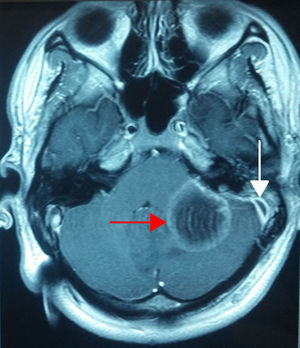

Caso 3Paciente masculino de 19 años de edad, referido a nuestro servicio por alteraciones de la marcha, estupor, otalgia y cefalea; papiledema a la fundoscopía. La TC de oídos mostró una otomastoiditis izquierda, mientras que la resonancia magnética nuclear (RMN) de cráneo evidenció una trombosis del seno sigmoides izquierdo y un absceso cerebeloso, razón por la cual se le realizó una mastoidectomía simple, la colocación de un tubo de ventilación, así como la exploración del seno sigmoides, con el drenaje y la evacuación del absceso por craniectomía de fosa posterior (fig. 3).